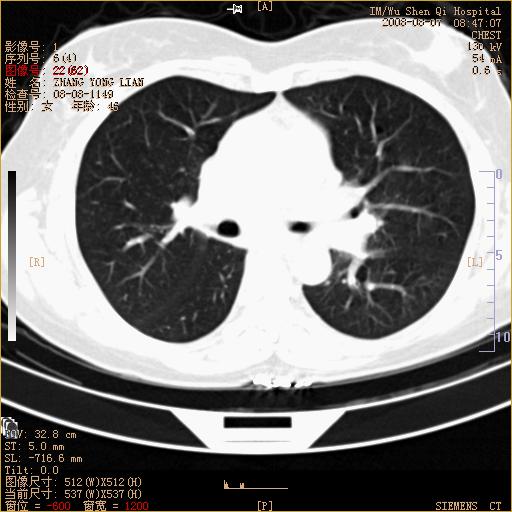

标题: CT15050:女,46岁,咳嗽胸痛一月余 [打印本页]

纵隔窗没发全,左下肺近胸膜处结节。有长毛刺,纵隔淋巴结增大,不排除恶性病变。

考虑肺癌

考虑左肺下叶后基底段周围型肺癌伴纵隔淋巴结转移可能性大。

左下肺ca并纵隔及左肺门区淋巴结转移。

1)考虑左肺下叶后基底段周围型肺癌伴纵隔淋巴结转移。2)脾内低密度灶,性质待定;不排除转移瘤可能。

考虑左肺下叶后基底段周围型肺癌伴纵隔及肺门淋巴转移。